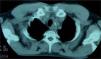

La TAC y la gammagrafía ósea no mostraron la presencia de enfermedad metastásica.

Las pruebas de imagen en los PNET nos permiten evaluar el tamaño y la extensión del tumor, estudiar la resecabilidad y detectar metástasis a distancia. Además, podemos analizar la estructura interna tumoral, lo cual nos puede ayudar a elegir la estrategia terapéutica más adecuada y predecir la posible respuesta al tratamiento9. Dick et al8 estudiaron la utilidad de la TAC y de la RMN en el diagnóstico y el seguimiento de un amplio grupo de pacientes con PNET y vieron que ambas se complementan ya que determinan la extensión tumoral del tejido blando con igual eficacia, pero mientras que en la TAC se ve mejor la afectación ósea y permite encontrar pequeñas metástasis pulmonares, la RMN es muy útil para detectar invasión de la pared torácica. Además

observaron que los tumores tendían a desplazar estructuras más que a encapsularlas. La ecografía de nuestro caso de PNET condíleo mandibular muestra una masa de ecogenicidad heterogénea de carácter sólido y bordes bien delimitados. Los hallazgos con ultrasonidos en los pocos casos publicados describen la lesión como hipoecoica, pudiendo presentar áreas quísticas anecoicas que corresponden a zonas de necrosis9.

En concordancia con nuestros pacientes, otros casos de PNET publicados presentan normalmente en la TAC y en la RMN un reemplazamiento de la señal normal con aumento en T2, disminución en T1 y captación postcontraste intravenoso de forma heterogénea8, 9. Los tumores de gran tamaño (aproximadamente 5 cm de diámetro) contienen algunas áreas quísticas o de necrosis, y raramente están calcificados.